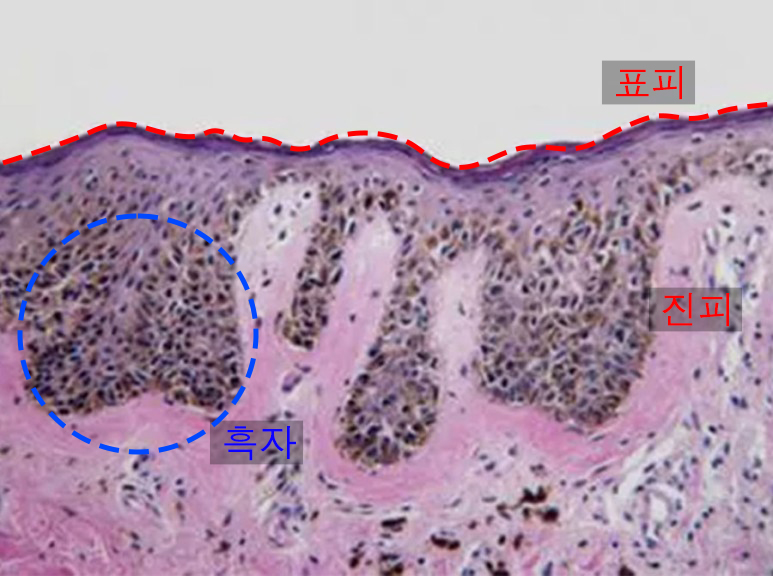

흑자가 있는 피부의 단면 모습입니다.

검은 좁쌀 같은 점들이 '멜라닌 색소'인데요. 이런 멜라닌 색소가 과도하게 증식하면서 기미, 흑자, 주근깨 등과 같은 색소질환을 유발합니다.

흑자의 경우 과증식된 멜라닌색소가 피부 진피까지 깊게 위치해 있고 피부 표면의 변형을 동반하기 때문에 출력 강도를 높여서 흑자를 무리하게 제거하려고 하면 과색소침착 발생 가능성이 매우 높아집니다.